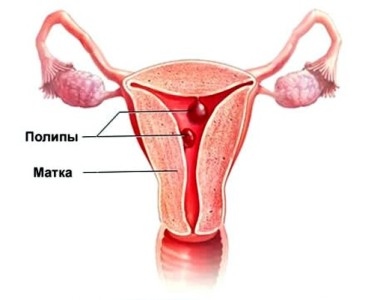

Якщо йдуть місячні дуже рясно і за один цикл це відбувається більше одного разу, не виключена ймовірність розвитку поліпів. Хронічний запальний процес може призвести до пошкоджень в порожнині матки, що і провокує часті виділення.